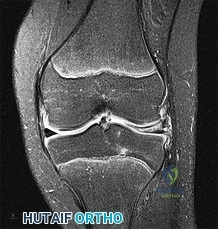

In a 14-year-old male with an osteochondritis dissecans (OCD) lesion of the knee, which radiographic location is most classic for this condition?

Which of the following locations is the classic and most common site for osteochondritis dissecans (OCD) lesions within the knee joint?